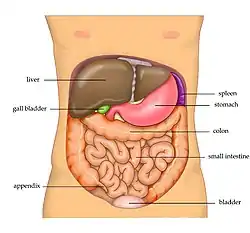

The abdominal cavity contains most organs of the digestive system, including the stomach, the small intestine, and the colon with its attached appendix. Other digestive organs are known as the accessory digestive organs and include the liver, its attached gallbladder, and the pancreas, and these communicate with the rest of the system via various ducts. The spleen, and organs of the urinary system including the kidneys, and adrenal glands also lie within the abdomen, along with many blood vessels including the aorta and inferior vena cava. The urinary bladder, uterus, fallopian tubes, and ovaries may be seen as either abdominal organs or as pelvic organs. Finally, the abdomen contains an extensive membrane called the peritoneum. A fold of peritoneum may completely cover certain organs, whereas it may cover only one side of organs that usually lie closer to the abdominal wall. This is called the retroperitoneum, and the kidneys and ureters are known as retroperitoneal organs.

Functionally, the human abdomen is where most of the digestive tract is placed and so most of the absorption and digestion of food occurs here. The alimentary tract in the abdomen consists of the lower esophagus, the stomach, the duodenum, the jejunum, ileum, the cecum and the appendix, the ascending, transverse and descending colons, the sigmoid colon and the rectum. Other vital organs inside the abdomen include the liver, the kidneys, the pancreas and the spleen.

Disease

Many gastrointestinal diseases affect the abdominal organs. These include stomach disease, liver disease, pancreatic disease, gallbladder and bile duct disease; intestinal diseases include enteritis, coeliac disease, diverticulitis, and irritable bowel syndrome.